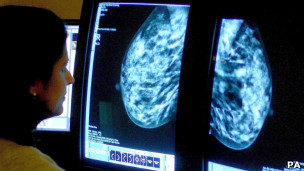

专家预计,子宫癌病例和死亡率的下降幅度最大,超过42%;乳癌死亡率下降28%;肠癌死亡率下降23%;前列腺癌死亡率下降16%。

专家认为,这项研究结果中最令人高兴的是,癌症里最主要的杀手,比如肺癌、乳癌、肠癌和前列腺癌的发病率和死亡率都呈下降趋势。